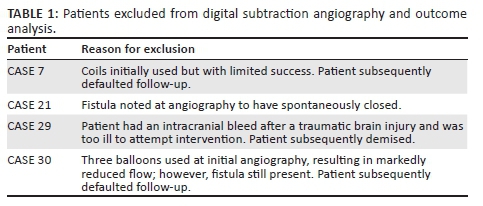

A total of four patients who did not undergo intervention or did not comply with follow-up were excluded from the subsequent analysis (n = 4). The reasons for exclusion are documented in Table 1. Although most patients presented with a single fistula, a few exceptions (n = 3) were noted with two simultaneous fistulas. For ease of statistical analysis, each fistula was analysed independently. A total of 36 fistulas in 34 patients were considered for analysis. DSA findings are presented in Table 2. The fistulas were classified according to their flow dynamic, cause and the presence of aneurysm or pseudoaneurysm. High-flow fistulas were present in all but two patients (n = 34, 94.44%). There was early filling of the affected CS in all patients. The fistulas did not favour a particular side and had predominantly anterior drainage only (n = 25, 69.44%). Aneurysms were identified in eight patients (22.22%) and psuedoaneurysms in two cases (5.56%). All patients passed the trial balloon occlusion test, suggesting adequate collateral blood flow.